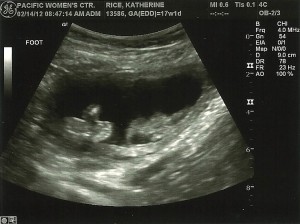

Other Goodness: Baby’s heartbeat was 169 beats/minute. And more ultrasound photos…

Baby Milestones: Baby is practice breathing and swallowing. According to the ultrasound, baby weighs about 7 oz.